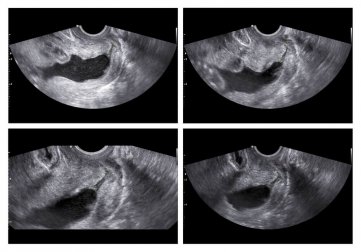

No entanto, se você foi afetada por alguns dos processos mencionados acima, você pode passar por uma ultrassonografia diagnóstica. Você também pode realizar um exame pélvico ou um ultrassom. Este último é capaz de medir o comprimento do colo do útero e sua abertura.

Normalmente, o colo do útero tem pelo menos 30 mm de comprimento. O risco de aborto ou parto predeterminado é inversamente proporcional ao comprimento do colo do útero:

- Menos de 25 mm: 18% de risco.

- Menos de 22 mm: 25% de risco.

- Menos de 15 mm: 50 % de risco.